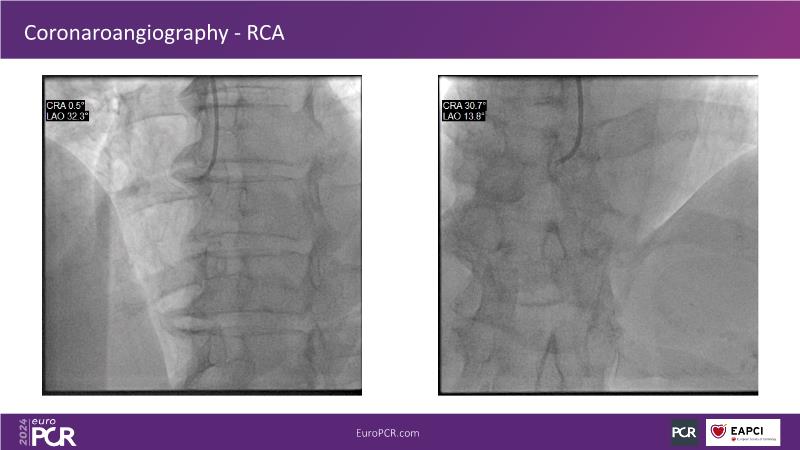

In this session, discover the effectiveness and safety of robotic PCI for both simple and complex lesions requiring additional devices like IVL, IVUS, laser, and FFR. Learn about the numerous benefits of robotics for patients and cathlab teams, including enhanced precision in wire navigation and stent positioning, full radioprotection, and reduced orthopedic injuries. Explore the growing interest in robotics within the interventional cardiology community, anticipate future technical advancements, and understand how AI will accelerate the integration of robotics and vice versa.

- To learn about a robotic PCI step-by-step from real-life experience